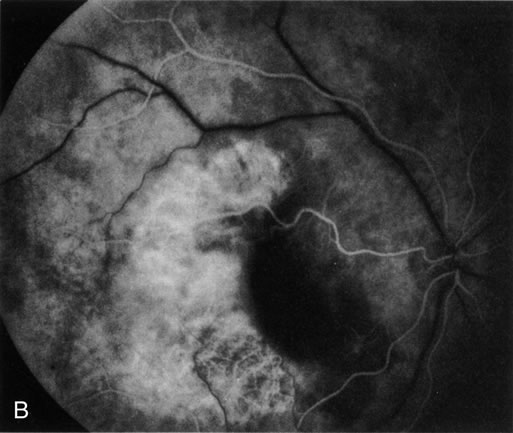

Gentamicin and tobramicin toxicity, which often result from inadvertent injection into the vitreous during cataract surgery, cause devastating retinal damage. In areas where high concentrations of gentamicin reach the retina there is obliteration of the retinal vasculature and ischemic necrosis of the retina (Fig. 43).269,270